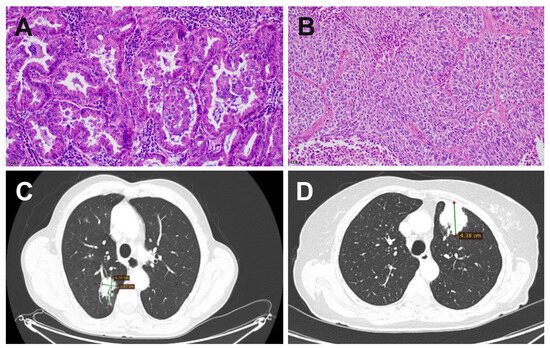

| Patient | WHO Classification | Histopathologic Grade | Pathologic Stage Classification (pTNM) |

|---|---|---|---|

| H22/518 F/75 | Squamous cell carcinoma | G3 | pT3, N0, Mx, PL0, V0/L1, R0 |

| H22/987 F/78 | Adenocarcinoma | G1 | pT2b, N0, Mx, PL0, L0/V0, R0 |

| H22/3994 M/64 | Squamous cell carcinoma | G2 | pT2a, pN0, Mx PL1, L0/V0, R0 |

| H22/9303 F/62 | Adenocarcinoma | G2 | pT2a, pN0, Mx PL1, L0/V0, R0 |

| H22/3486 F/63 | Adenocarcinoma | G2 | pT1b, N0, Mx PL1, L0/V0, R0 |